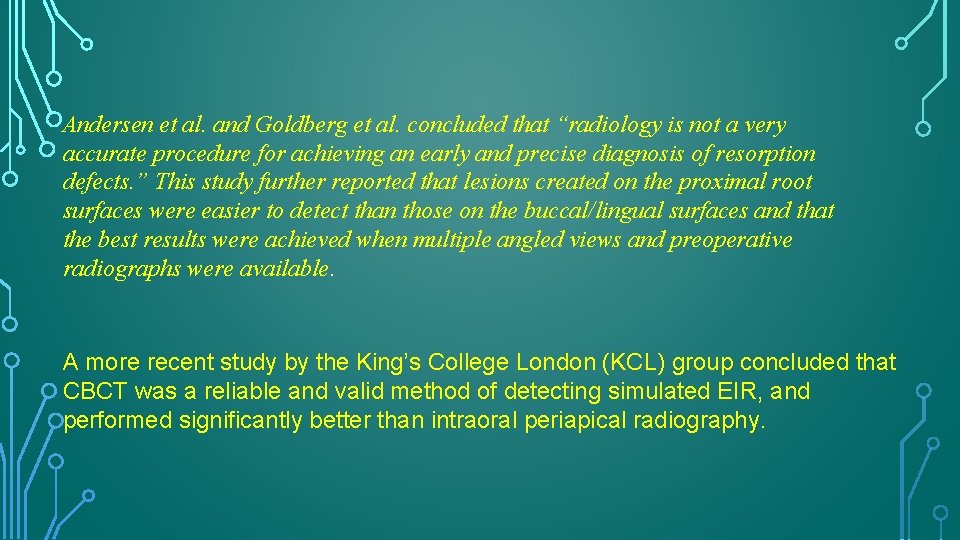

DIAGNOSIS • Solely on the radiographic demonstration of the process. • IOPAR and panoramic radiography is less efficient to detect small resorption lesions especially on buccal or lingual surfaces. • CBCT is superior to conventional radiography in diagnosing and determining the extent of resorption on root surfaces

Andersen et al. and Goldberg et al. concluded that “radiology is not a very accurate procedure for achieving an early and precise diagnosis of resorption defects. ” This study further reported that lesions created on the proximal root surfaces were easier to detect than those on the buccal/lingual surfaces and that the best results were achieved when multiple angled views and preoperative radiographs were available. A more recent study by the King’s College London (KCL) group concluded that CBCT was a reliable and valid method of detecting simulated EIR, and performed significantly better than intraoral periapical radiography.